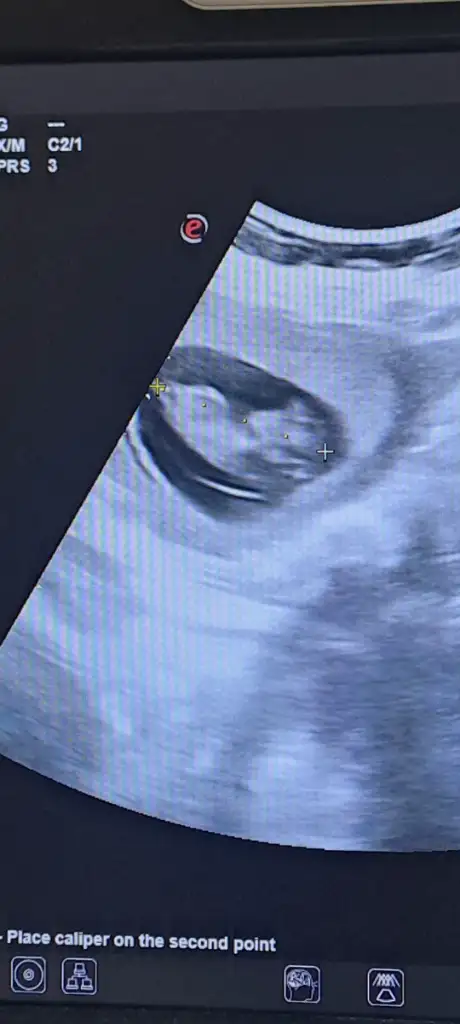

Keseden cinsiyet tahmin eden var mı cinsiyet takvime göre erkek cıkınca ama neyimiz olacak çok merak ediyorum doğrusu

Kızlar varsa tahmin bende alabilirim 😍